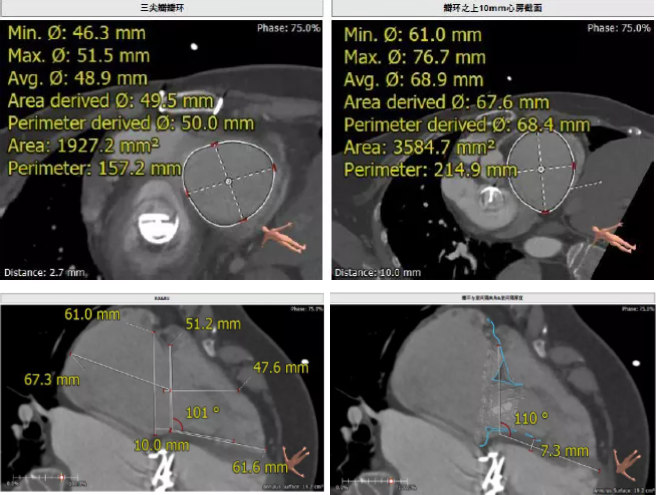

術(shù)前CT評估